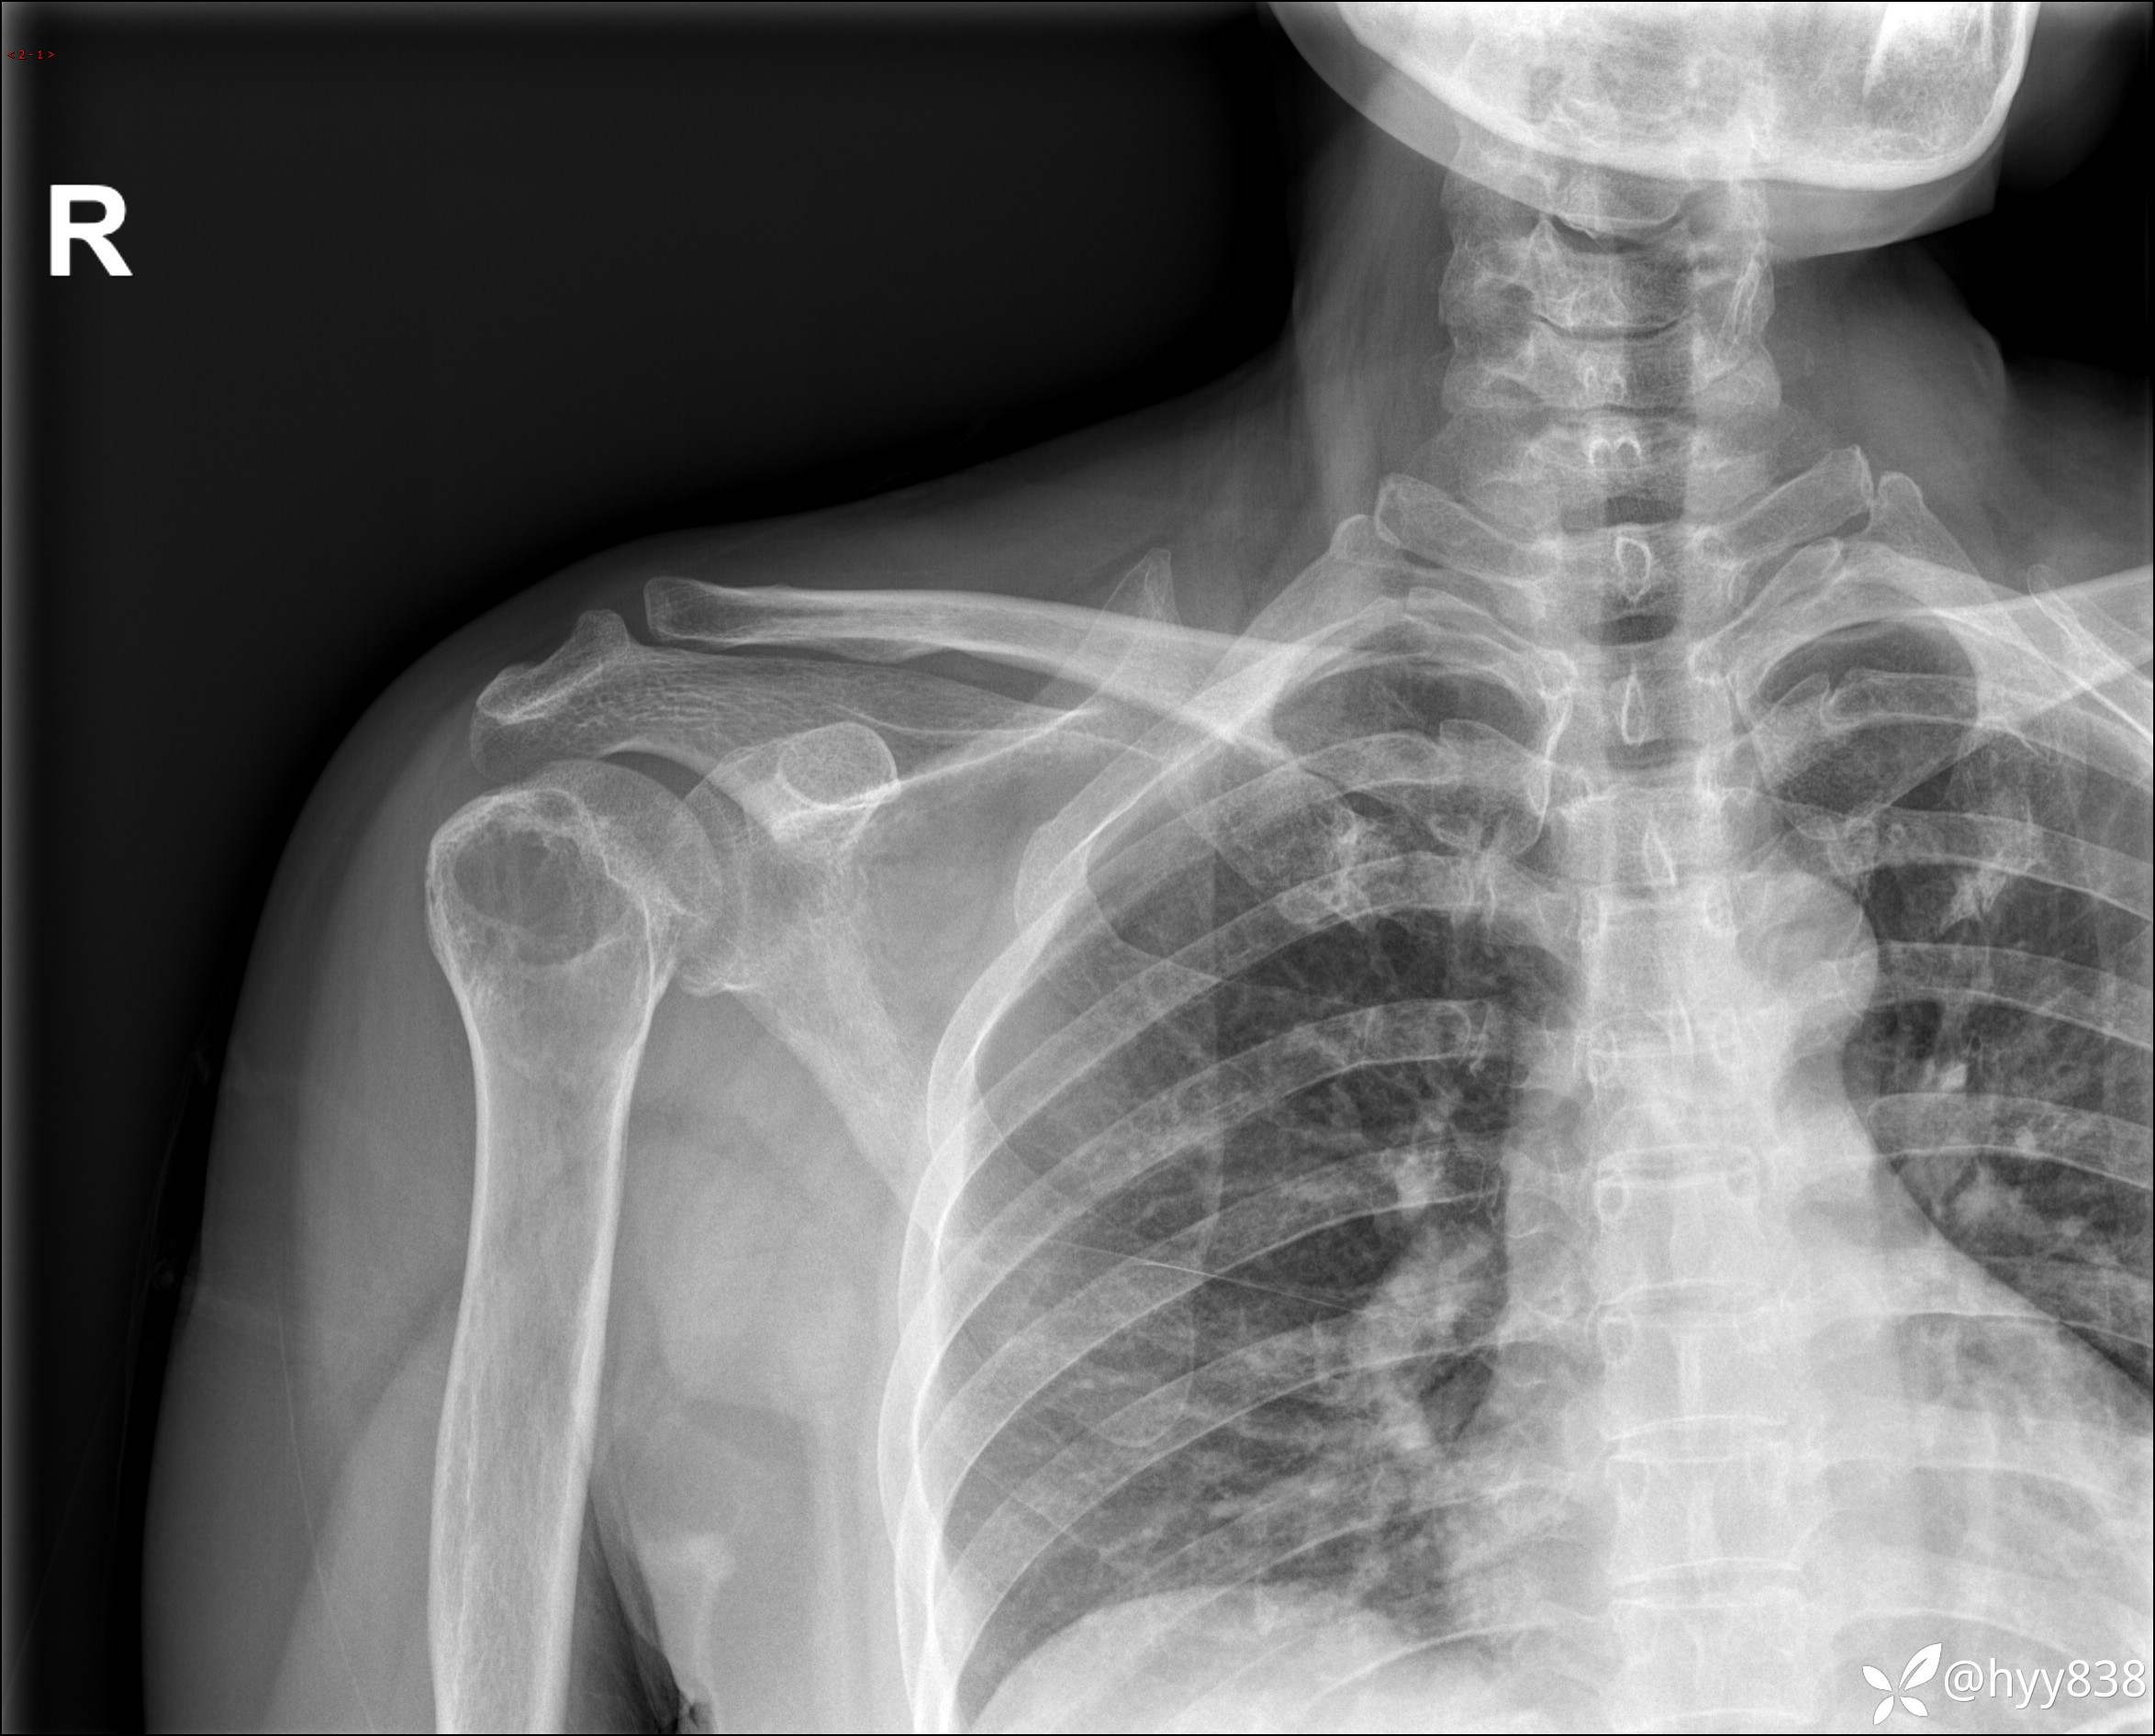

右肩关节平片